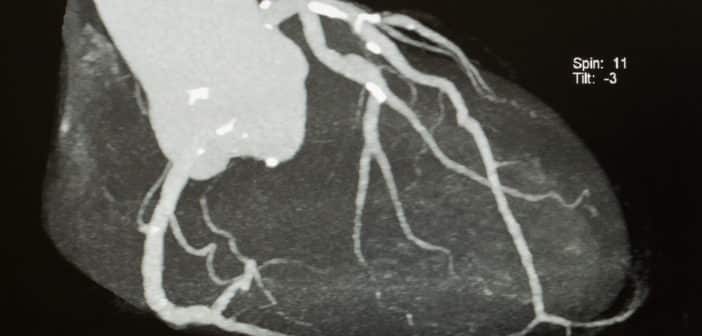

L’imagerie cardiovasculaire non invasive – le scanner cardiaque en particulier – joue un rôle central dans l’évaluation préopératoire des patients candidats à une intervention structurelle, qu’elle soit valvulaire, fermeture d’auricule ou du septum interatrial. Le scanner fournit en effet un large éventail d’informations cruciales pour sélectionner les patients qui en bénéficieront le plus et dont la procédure se fera avec un maximum de sécurité.

Les protocoles de tomodensitométrie doivent être optimisés en fonction de la technologie disponible : par exemple, pour le remplacement valvulaire aortique percutané (TAVI), deux acquisitions distinctes sont souvent nécessaires pour couvrir une large plage anatomique allant des axes sous-claviers aux artères fémorales, ainsi qu’une acquisition de la racine aortique synchronisée sur l’ECG. Pour la pathologie mitrale, tricuspide et les maladies du septum atrial (foramen ovale perméable [FOP] et communication interauriculaire [CIA]), on fera une acquisition injectée du massif cardiaque synchronisé à l’ECG. Pour la fermeture d’auricule, on fera également une acquisition au temps tardif (60 à 90 secondes après l’injection) [1].

Les images doivent être reconstruites à 1,0 mm ou moins pour permettre des études multiplanaires précises. Par conséquent, un scanner avec 64 détecteurs minimum ou à double source est requis.

Le scanner cardiaque est de plus en plus souvent demandé pour une étude de la valve aortique : il permet de préciser le caractère tricuspide ou bicuspide, le degré de calcification ou le risque de mismatch avant chirurgie dans tous les cas où l’échographie[...]